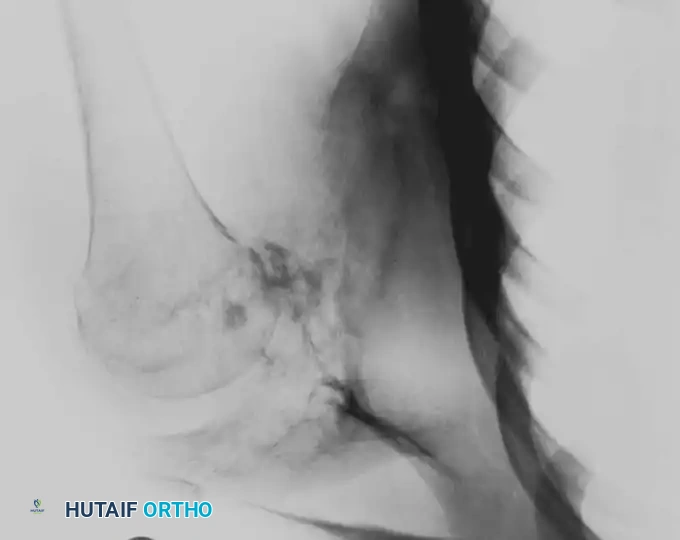

Intraoperative Imaging and Margin Assessment

Continuous intraoperative assessment using fluoroscopy and frozen section pathology is mandatory. The following images demonstrate various stages of complex upper extremity resections, allograft preparations, and prosthetic implantations across the humerus and elbow joint.